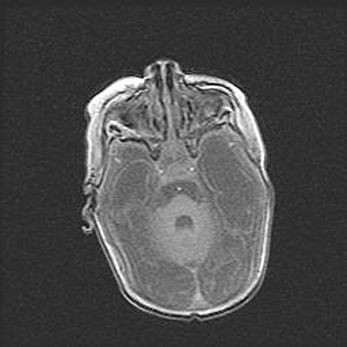

Лейкомаляция с кистозно-глиозной дегенерацией головного мозга.

Возраст: 2 месяца 25 дней

Вес: 6400 г

Окружность головы: 40 см

Срок гестации: 41 неделя

Лейкомаляцию относят к ишемически-гипоксическим повреждениям головного мозга, диагностируемым у новорожденных. При лейкомаляции в головном мозге обнаруживают очаги некроза, возникшие после тяжелой гипоксии и нарушения кровотока. В процессе морфогенеза очаги проходят три стадии: 1) развития некроза, 2) резорбции и 3) формирования глиозного рубца или кисты. Перивентрикулярная лейкомаляция (ПЛ) встречается примерно в 12% случаев среди новорожденных, обычно – у недоношенных детей, причем, частота ее зависит от массы, с которой младенец появился на свет. Наибольшее число малышей страдает лейкомаляцией, если масса при рождении 1500-2500 г.